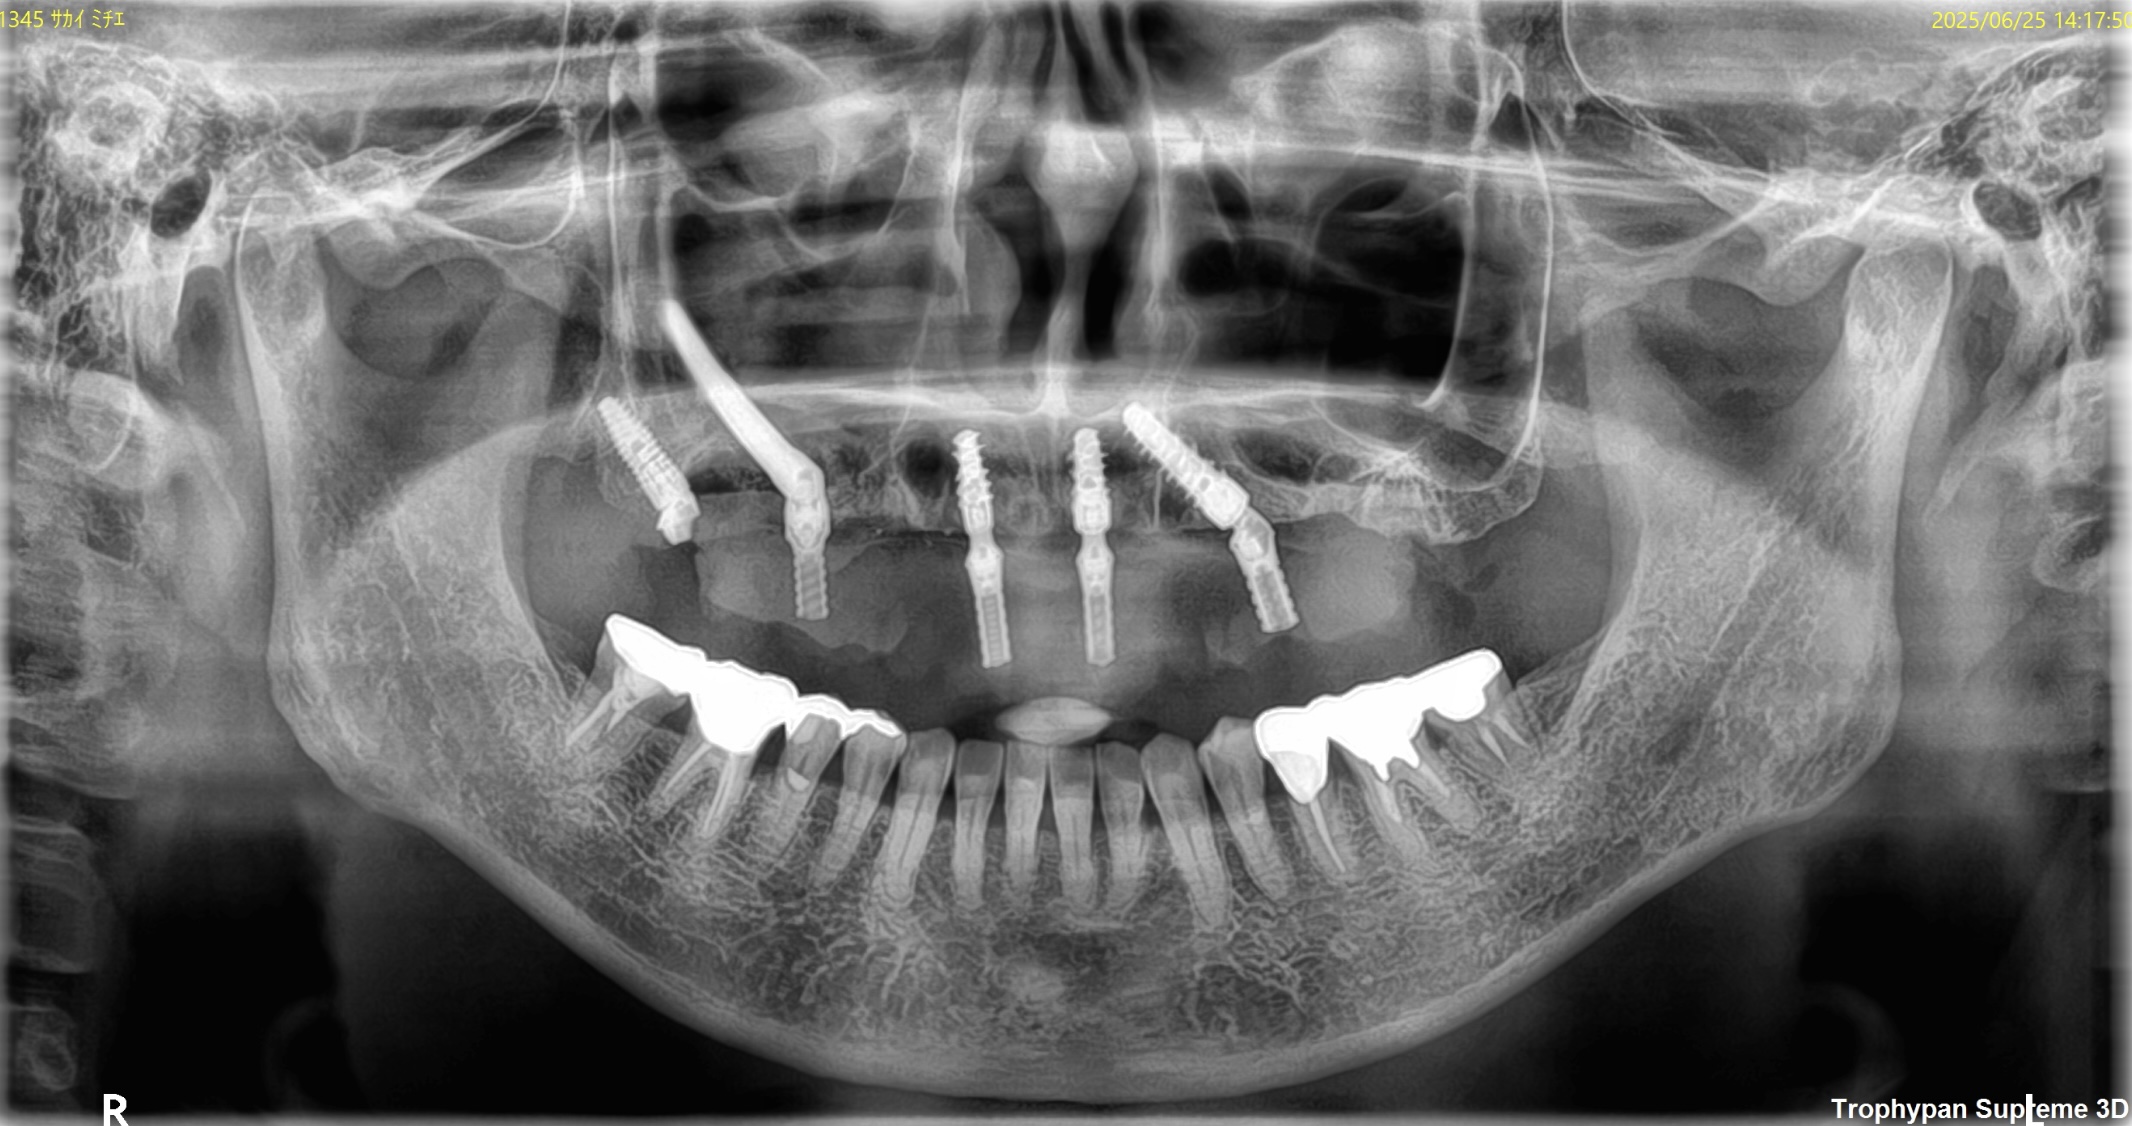

CASE

3